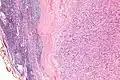

High mag.

IPMs are diagnosed by examination of the tissue by a pathologist. They have a rim of peripheral lymphoid tissue (remnant of a lymph node) and consist of spindle cells with nuclear palisading. Red blood cell extravasation is common and blood vessels surrounded by collagen with (fine) peripheral spokes (amianthoid fibers) are usually seen.[2]

Immunostains for smooth muscle actin and cyclin D1 are characteristically positive. The main histologic differential diagnosis is schwannoma.